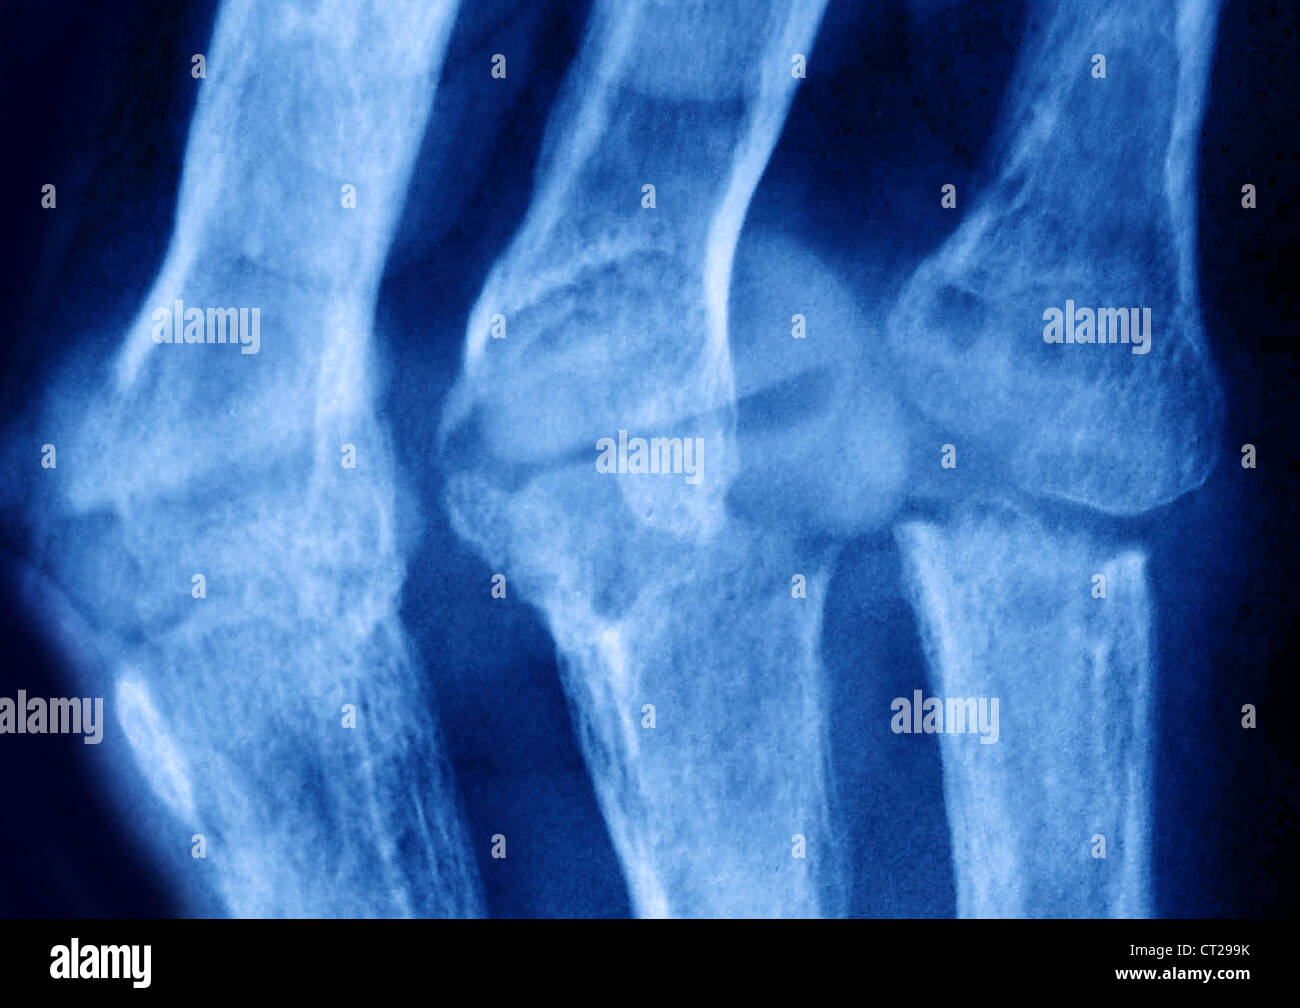

From www.alamy.com

Rheumatoid arthritis, Xray Stock Photo Alamy Why Do I Need A Chest X Ray For Rheumatoid Arthritis costochondritis is not arthritis in the ribs or the chest and isn't directly related to ra, but inflammation from ra can. learn what types of imaging scans are most effective in detecting and monitoring ra. chest ct or hrct features include: contact your doctor promptly if you have rheumatoid arthritis and experience any unexplained breathing. . Why Do I Need A Chest X Ray For Rheumatoid Arthritis.